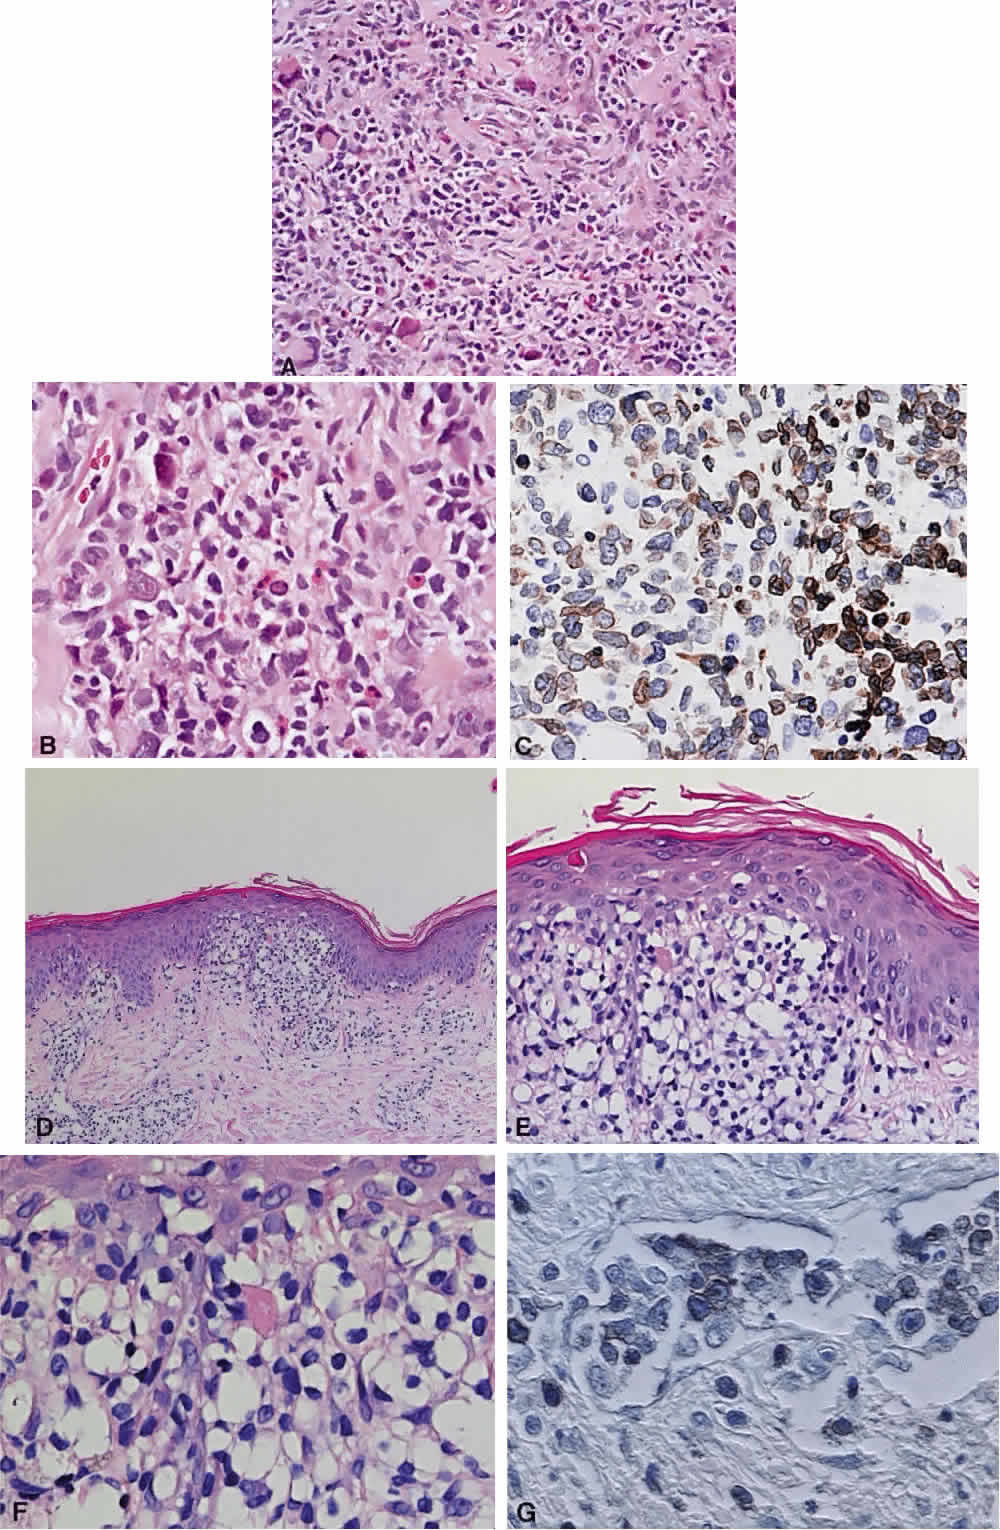

Numerous attempts have been made to classify lymphoid processes for clinical management and prediction of prognosis. Early classifications included only disease localized to the lymph node, which made classification of extranodal disease difficult and inaccurate. The Rappaport classification, first developed in 1956 and then modified in 1978, attempted to categorize lymphomas in two ways, first, using cytologic characteristics identified by conventional stains, and second, distinguishing between the follicular and diffuse growth pattern histologically38,39 (Table 3). The distinction of nodular, or follicular, and diffuse growth was considered useful because of the generally indolent nature of follicular growth, in which the tumor cell aggregates resemble germinal centers and disrupt the normal architecture of the node, compared with the appearance of diffuse growth, in which the lymph node is completely obliterated by a dense monotonous sheet of lymphocytes. In subsequent years, however, it was found that the descriptive growth pattern and cytogenetic characteristics of the Rappaport system did not predict prognosis reliably and were biologically inaccurate. The complexity of correlating degrees of differentiation, mitotic activity, and cytologic characteristics to prognosis have made lymphomas difficult to classify and have led to subsequent systems. The second system, proposed by Lukes-Collins in 1974, classifies lymphoma histologically according to its normal counterpart B-cell, T-cell, or null cell origin40,41 (see Table 3). Histologically, cells may appear small cleaved, large cleaved, small noncleaved, or large noncleaved, depending on the stage of B-cell arrest during normal transformation to immunoblast. Ninety percent of lymphomas are of B-cell origin, and the null cell also usually is of B-cell origin, although 10% may originate from T cells or histiocytes.42,43 Burkitt's lymphoma, the only lymphoma common in children, is a B-cell variant with a background of reactive histiocytes. As a result of histologic classification by Lukes-Collins, 76% of histiocytic lymphomas according to the Rappaport system were found to be not of histiocytic origin but of lymphocytic origin.40,44 The third system, the Working Formulation devised by the National Cancer Institute in 1982, attempted to predict prognosis by grouping lymphoma according to natural history, response to therapy, and overall survival.45 Three broad categories were established in terms of 5-year survival rates, the low-grade with a 50% to 70% survival rate, intermediate with 35% to 45%, and high grade with 23% to 32% (see Table 3). Orbital reactive hyperplasia, a relatively low-grade lesion, can be associated with systemic disease, whereas malignant or high-grade orbital lymphomas may be isolated findings. The Ann Arbor Staging Classification for Hodgkin's and non-Hodgkin's lymphomas was developed to stage disease based on systemic areas of involvement as a means of establishing a baseline for treating disease and following clinical progression46 (Table 4). Histologic classification, however, has been recognized as more useful than localization in the clinical management of nonHodgkin's lymphoma.47

While the Lukes-Collins and Working Formulation classifications were in wide use in the United States, the European literature made references to the Kiel and updated Kiel classifications, which led to disparities in classifying lymphoma. Another classification proposed by Jakobiec and coworkers was the most comprehensive classification available for orbital disease but failed to integrate systemic lymphoma, which is known to be associated in approximately half of cases.1 The most recent classification has made the system universal, comprehensive, and useful to interdisciplinary teams that characteristically manage patients with lymphoma. The International Lymphoma Study Group in 1994 developed the Revised European-American Lymphoma (REAL) classification (Table 5), which classifies lymphoid disease by the cell of origin into B-cell, T-cell, and natural killer cell lymphomas, leukemias, myeloma, and variants of Hodgkin's disease26 (Fig. 4). The identification of the putative benign progenitor cells has been inferred through the use of cell marker studies. The results of molecular genetic studies to identify immunoglobulin gene rearrangements and cytogenetic studies to detect chromosomal translocations in monoclonal proliferations have also been incorporated. A significant contribution of the REAL classification has been to incorporate primary extranodal lymphomas as recognizable and classifiable entities. As a result, new variants in this list include lymphoplasmacytic lymphoma, mantle cell lymphoma, marginal zone B-cell lymphoma, particularly mucosal-associated lymphoid tissue (MALT) lymphoma, subclasses of large cell lymphoma, and the natural killer cell lymphomas. Comparisons of the REAL classification to the Working Formulation and the Kiel classification are shown in Tables 6 and 7, respectively.48 The first series of 112 orbital lymphomas using the REAL classification reported the accuracy and utility of the system in classifying orbital lesions and predicting prognosis in combination with currently available immunophenotyping and immunocytogenetic studies.49 The REAL classification does not classify disease based on the degree of differentiation or clinical prognosis. However, a proposed prognostic scheme has been developed in accordance with the REAL classification28 (Table 8). In this text, tumor nomenclature adheres as strictly as possible to the REAL classification.

CLINICAL PRESENTATION OF SYSTEMIC NON-HODGKIN'S LYMPHOMA